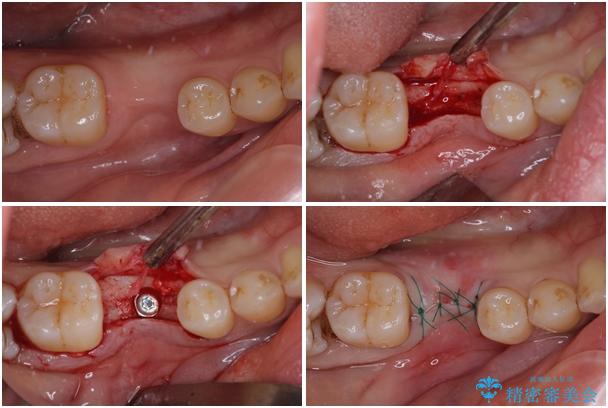

治療途中

• 空いている時間を利用して通院 奥歯のインプラント治療 治療途中画像